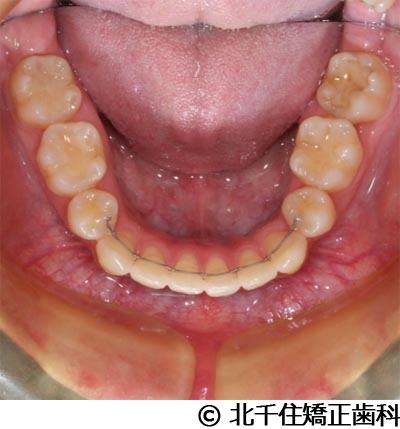

【症例3】叢生

- 治療前

- 治療後

- 治療名

- 叢生

- 費用

- 1,125,000円(税込)

- 期間

- 2年1ヵ月

- 治療回数

- 26回

- 通院頻度

- 1ヵ月ごと

- 年齢・性別

- 19歳3ヵ月・女性(初診時)

治療内容

-

患者様の症状

主訴:デコボコ、口元の突出

治療方法

上下顎第一小臼歯4本を抜歯してワイヤー矯正(セラミックブラケット)。

治療結果

叢生に対し抜歯を併用した矯正治療により、歯列および咬合関係の調整を行った症例である。治療後は保定装置を使用し、歯列および咬合の安定維持を目的として定期的な経過観察を行っている。

※治療結果は個人差があります。

治療を行う上での注意点(リスク・副作用)

歯磨き不良に伴うカリエスや歯周病、歯根吸収など。